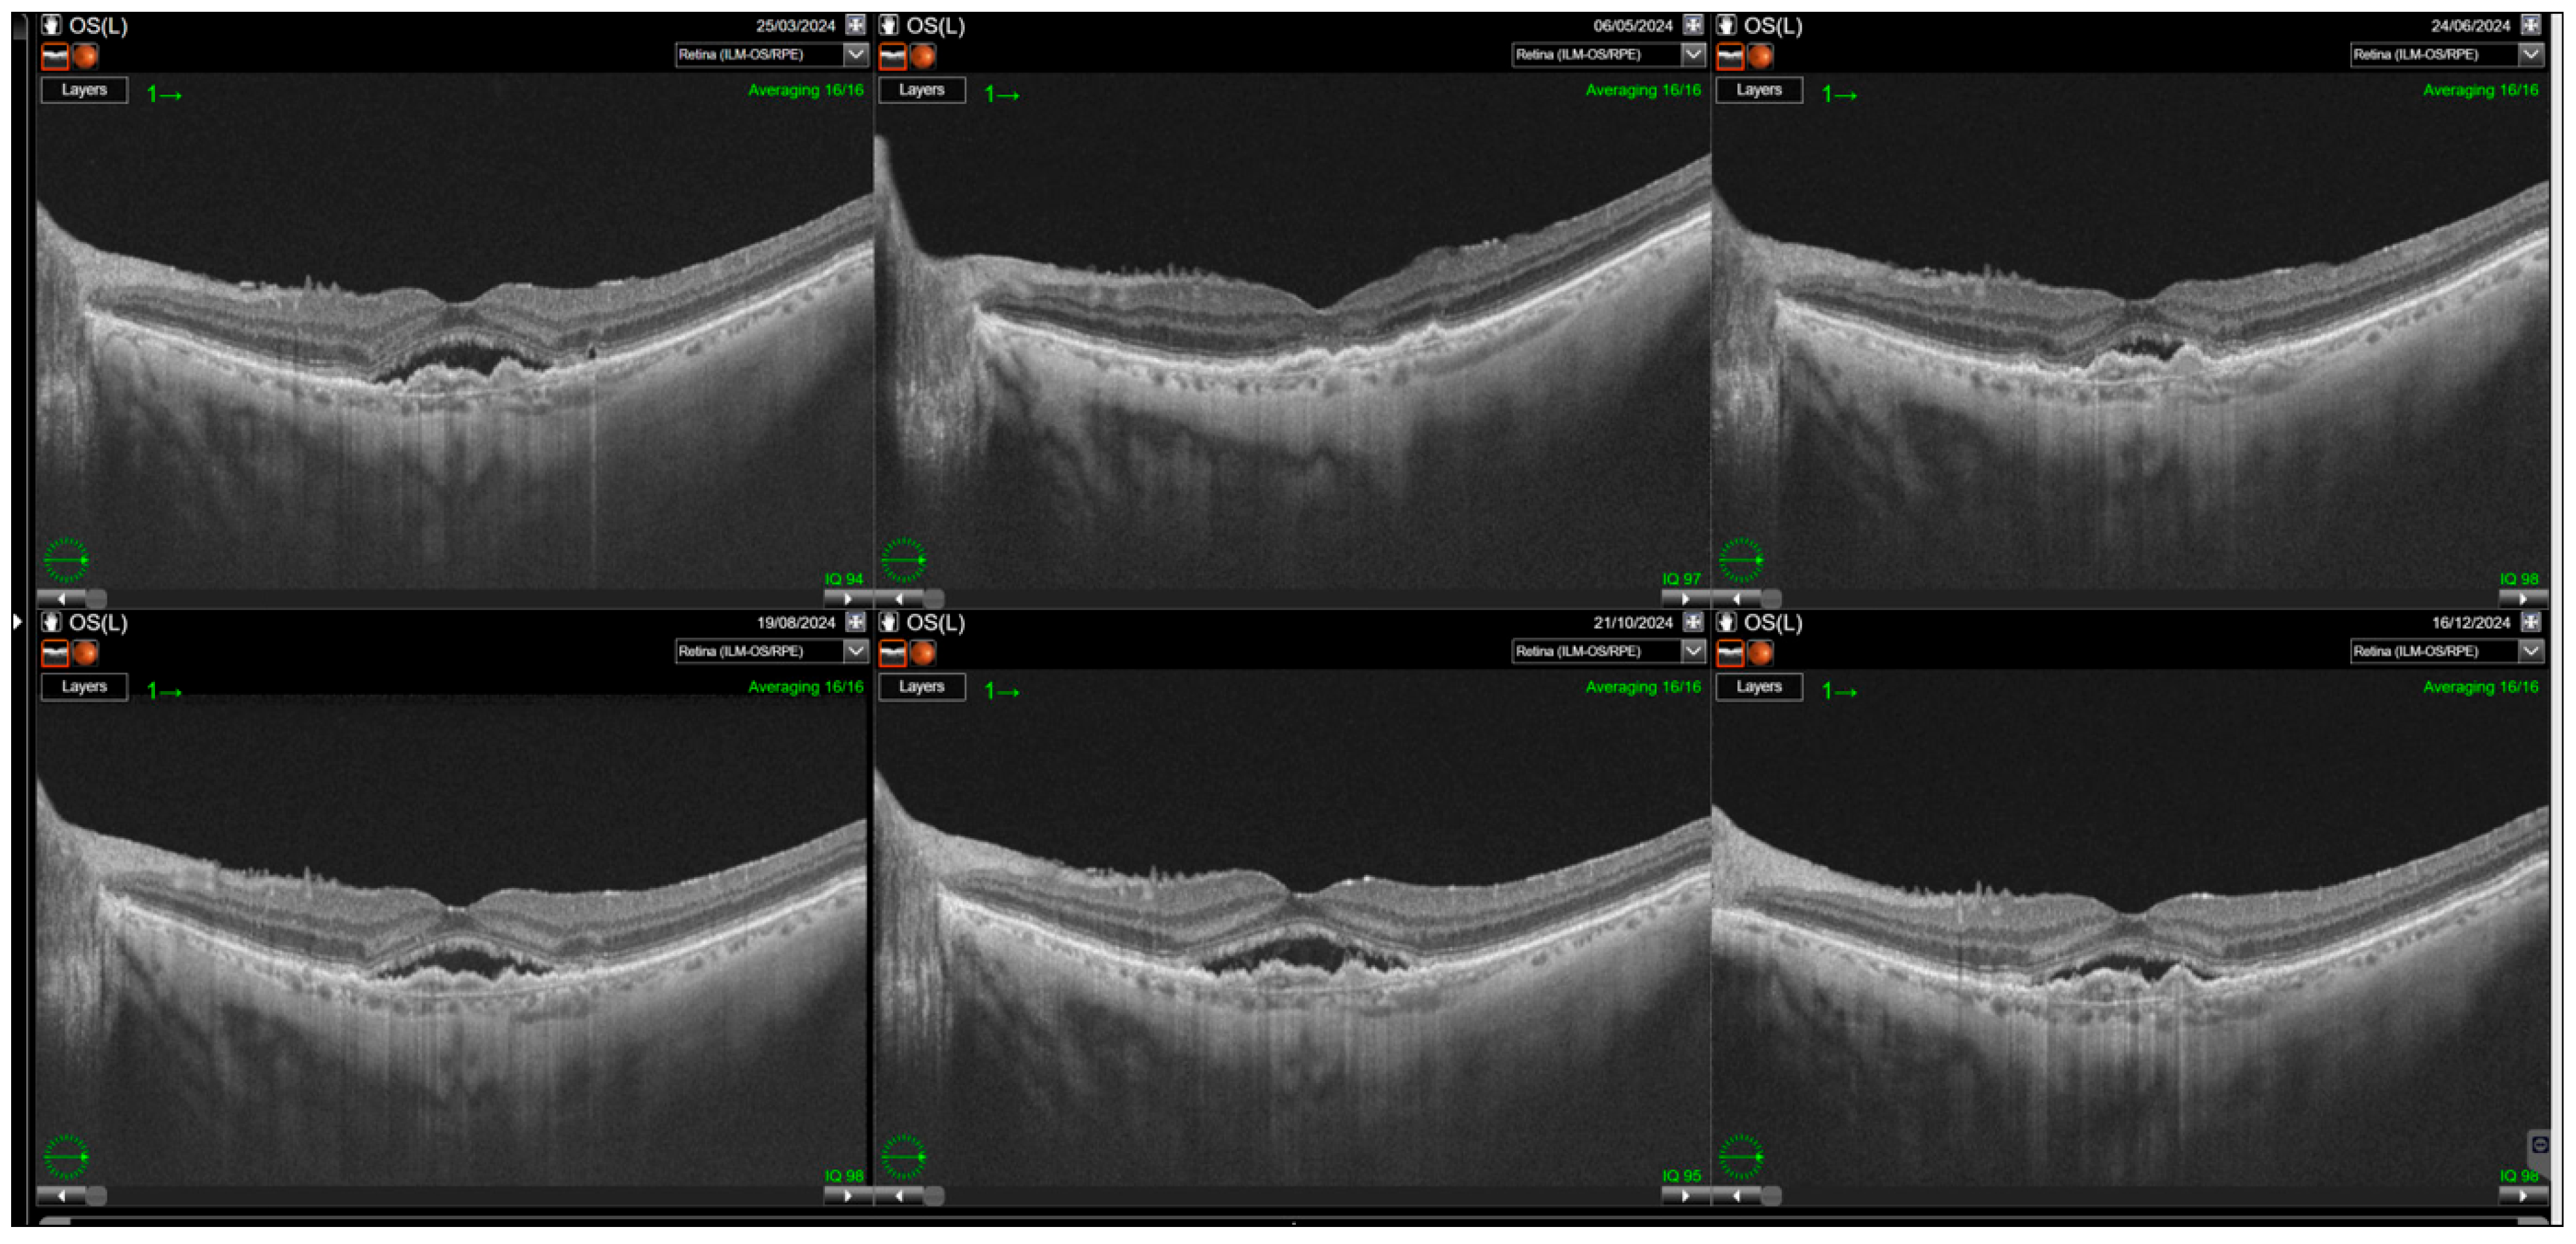

3. Results

3.2. Central Subfoveal Retinal Thickness (CST)